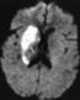

Cerebral infarction

A cerebral infarction is an area of necrotic tissue in the brain resulting from a blockage or narrowing in the arteries supplying blood and oxygen to the brain. The restricted oxygen due to the restricted blood supply causes an ischemic stroke that can result in an infarction if the blood flow is not restored within a relatively short period of time. [Source: Wikipedia ]